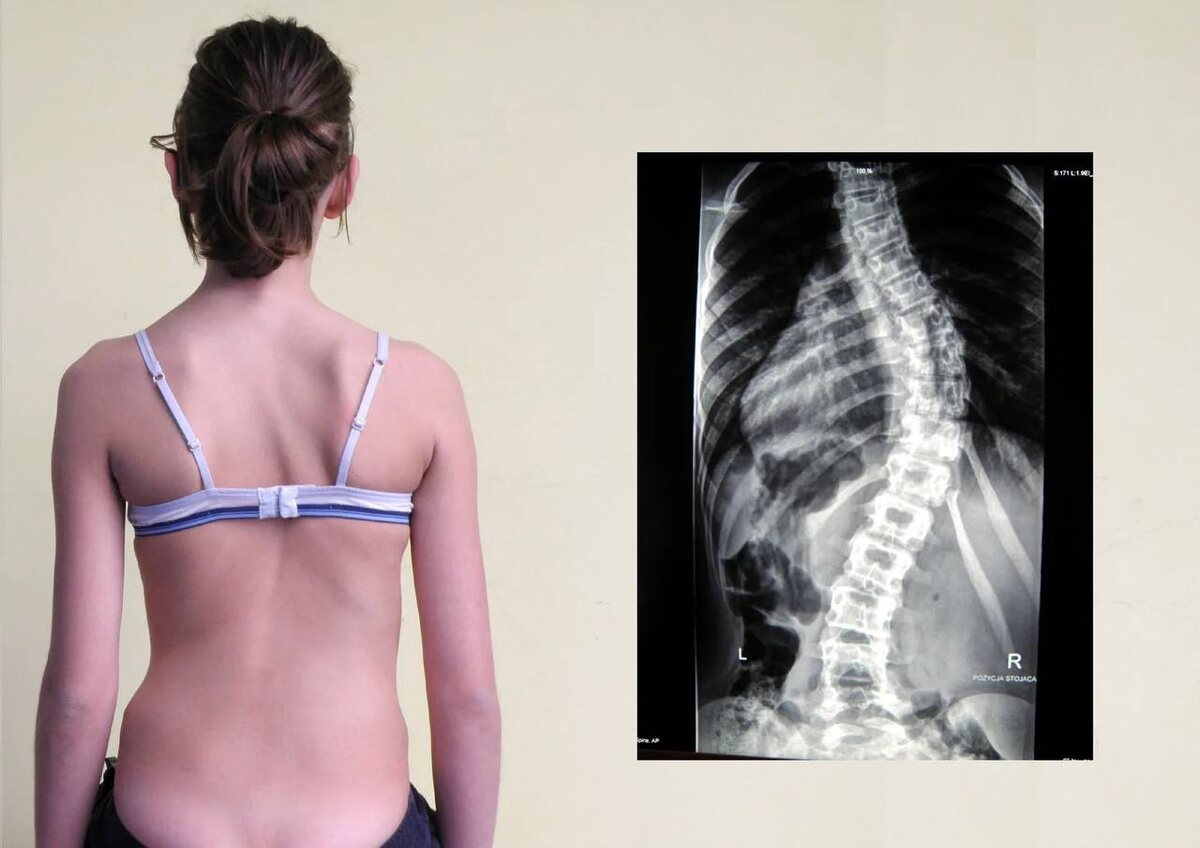

Сколиоз — не всегда про позвоночник. Часто про то, что давит изнутри.

Ко мне обращаются мамы с запросами на частые простуды, аллергию, энурез, а бывает и со сколиозом. Вроде бы обычная история, поставили диагноз, назначили корсет, гимнастику, массаж. Но ничего не меняется или меняется медленно. Если сколиоз не врождённый, а приобретённый — значит, он не просто «взялся ниоткуда». И часто за этим стоит не тело, а душа ребёнка, которая живёт в этом теле и пытается как-то справляться с тем, что происходит вокруг. И если вокруг него не безопасно, он начинает сжиматься. Если ребёнку постоянно говорят: 🔻 "Нельзя" 🔻 "Ты ещё маленький, тебе не понять" 🔻 "Не выдумывай, ты этого не чувствуешь" 🔻 "Ты должна, ты обязан" 🔻 "Кого волнует твоё мнение?" ...его характер, как росток, пробивается сквозь бетон. Где-то гнётся, где-то ломается, где-то замирает. А тело в это время адаптируется, защищается. Скручивается. 👀 У многих детей со сколиозом — авторитарные родители, которые из лучших побуждений: ▪️не слышат, что чувствует ребёнок, ▪️не разрешают иметь своё мнение